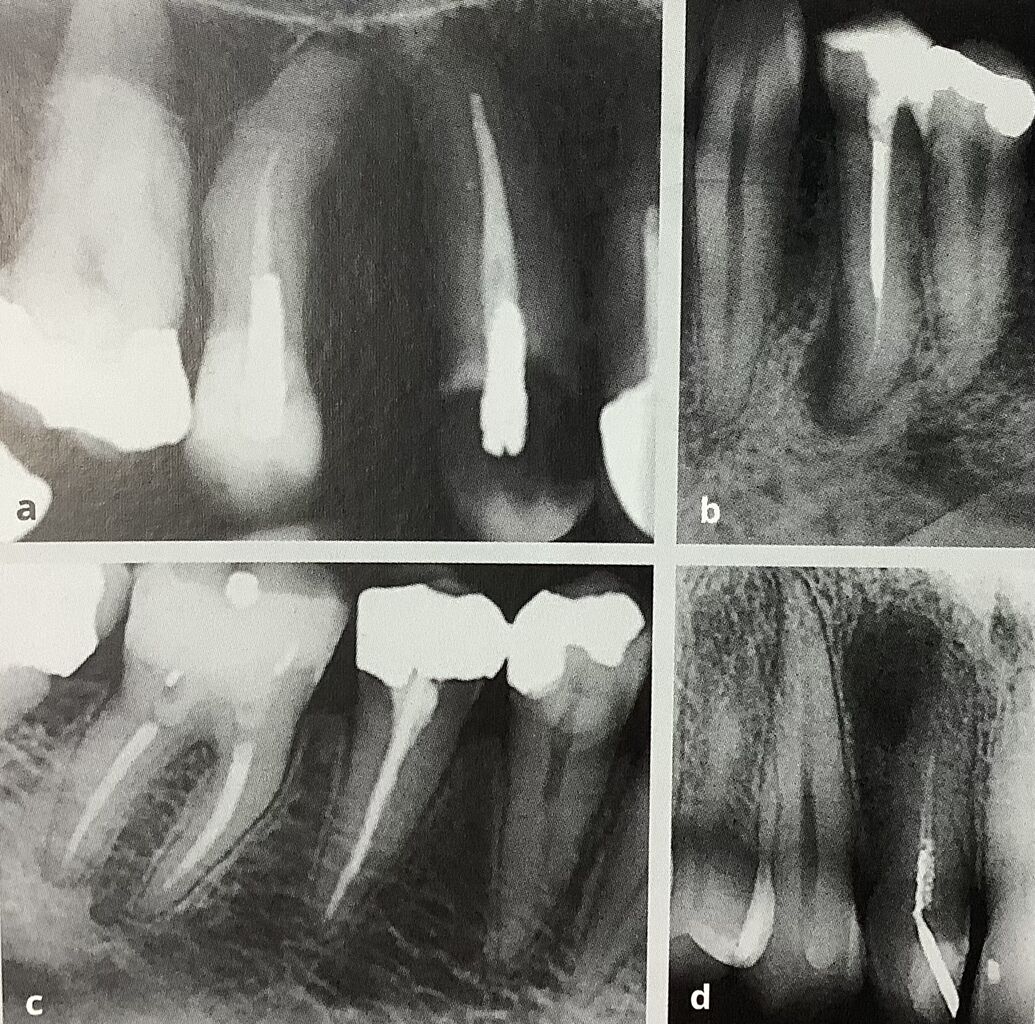

左がいつものレントゲンです。

根っこに入っているネジ、ポストが変な方向です。

右はCTで、裏側に突き抜けています。

これはチョウっと見え難いですが、

ステップが、段差ができてたり、

器具が折れ込んでいるものです。